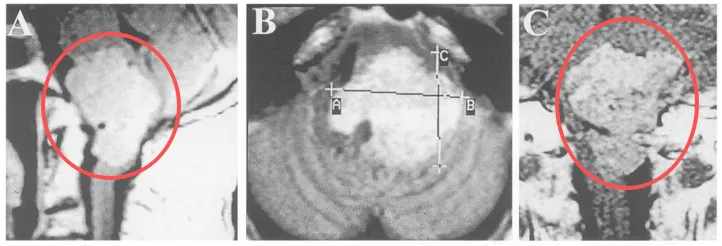

术前MRI与CT评估

MRI是目前确诊枕骨大孔区脑膜瘤的重要手段。T1加权像多呈等信号或略低信号,T2加权像为等信号或高信号,部分病例可见囊变坏死、出血征象,肿瘤边界大多清晰。静脉注射钆造影剂增强扫描后,肿瘤呈现显著均匀强化,大部分病例可见典型"脑膜尾征"。

同时,MRI矢状位和冠状位图像可直接显示延髓、颈髓受压情况。当肿瘤侵犯脑干软脑膜时,T2加权像可见脑干区域高信号改变,FLAIR像表现更为明显,这常提示脑水肿存在,肿瘤压迫脑干导致水肿往往影响肿瘤切除程度及术后并发症发生。增强结果可反映肿瘤血供情况,轴位及冠状位图像也有助于判断肿瘤与同侧椎动脉及周边硬脑膜的关系。MRI也是鉴别枕骨大孔区肿瘤与颈椎病、寰枕畸形等重要手段。

图示:典型枕骨大孔腹侧脑膜瘤,伴沿斜坡走行的鼠尾征(上图),肿瘤常侵犯颈静脉孔增加手术难度,需采用远外侧入路切除肿瘤。